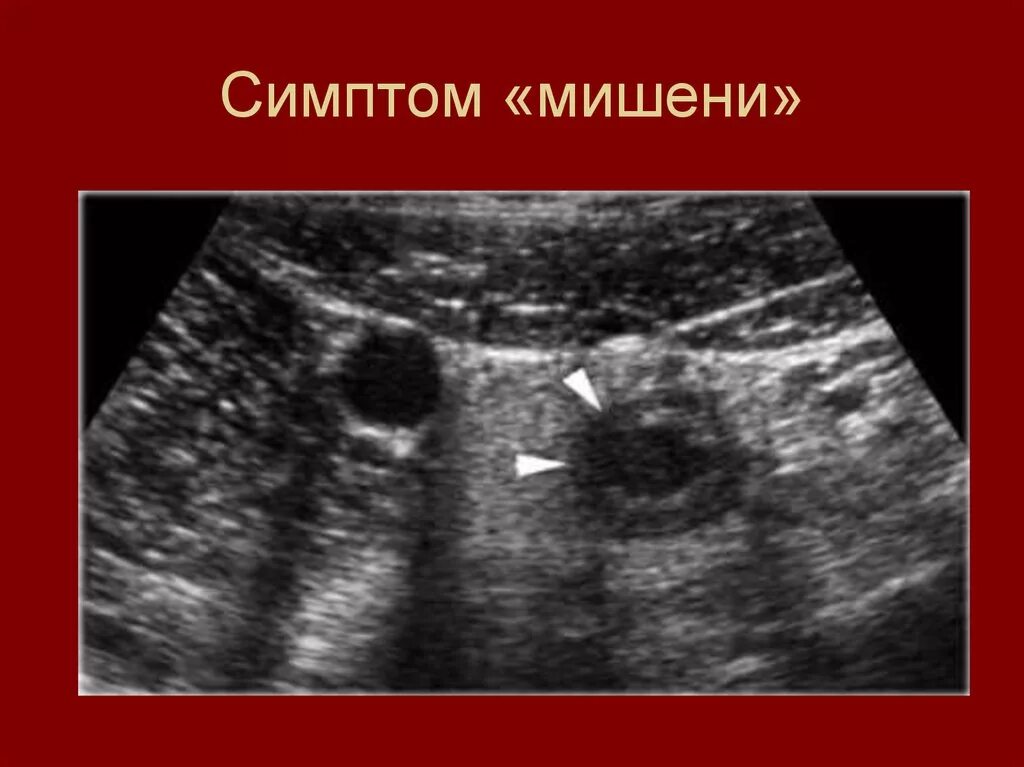

Аппендицит на узи можно ли